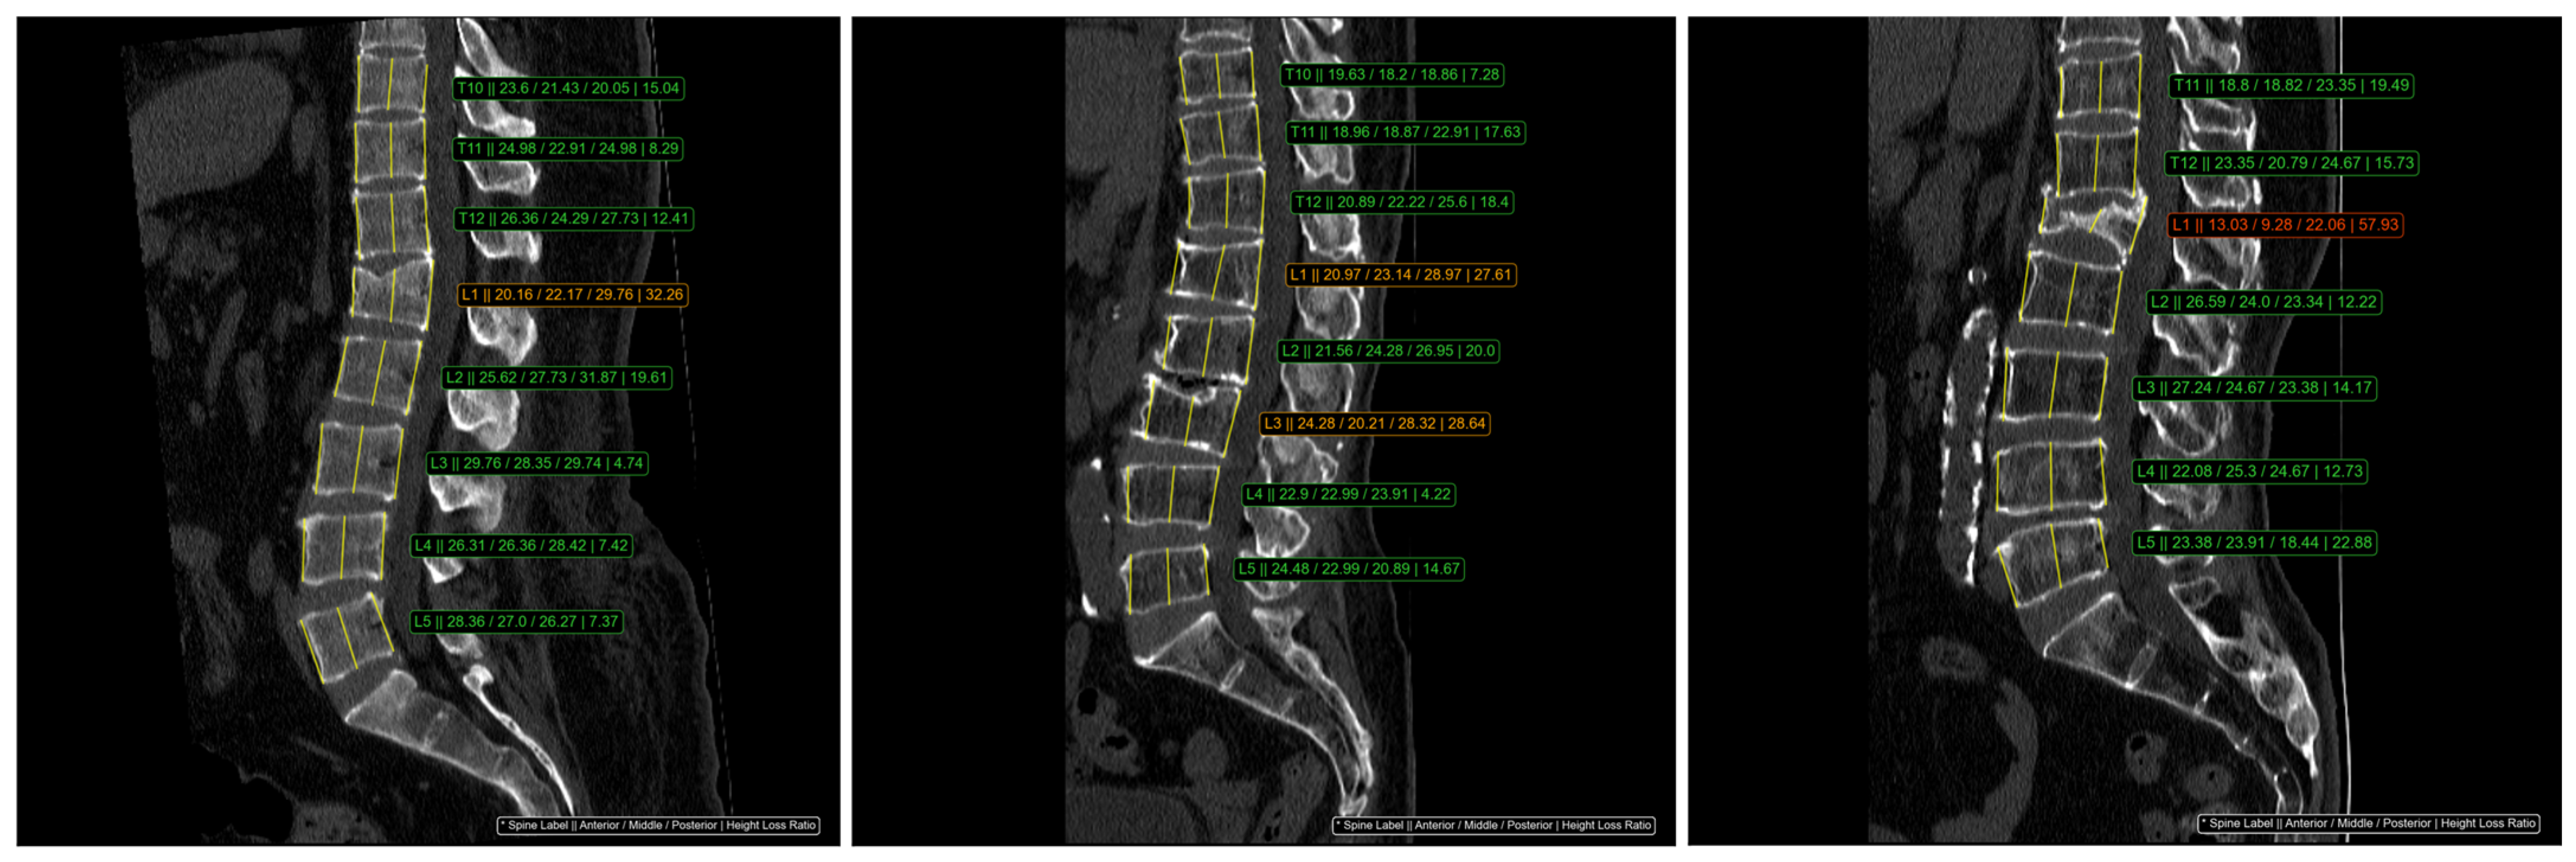

The Genant classification method was utilized to assess the height of three specific regions in each vertebral body. According to this system, vertebrae were classified into four categories: normal (HLR < 20%), mild compression (20% ≤ HLR < 25%), moderate compression (25% ≤ HLR < 40%), and severe compression (HLR ≥ 40%) [6]. The ClariVBA program automatically measured the height of the three regions for each vertebral body, calculated the height loss ratio, and provided quantitative values adjacent to each vertebra. Moderate fractures were displayed in orange, severe fractures in red, and mild fractures, which could exhibit inter- or intra-observer variation, were displayed in the same green color as normal vertebrae (Figure 1). In this study, vertebrae with mild compression were not classified as VCFs.

Figure 1.

An example of automatic HLR measurement from DL-software, ClariVBA (Ver1.0, ClariPi Inc., Seoul, Republic of Korea). The consecutive values in the image, indicated with an * symbol, were spine label, anterior height, middle height, posterior height, and HLR. Moderate (Genant grade 2) VCF is orange and severe (Genant grade 3) VCF is red. The green color represented the normal vertebrae.